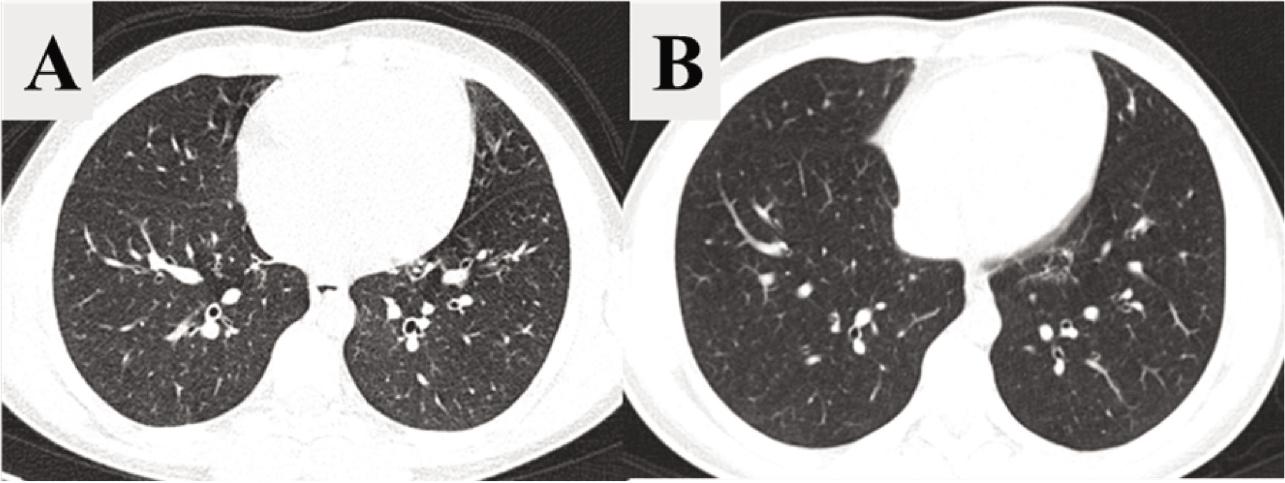

Figure 2.

Figure 3.

| Total Bhalla score | 14.55 | 18.27 | 3.73 | (2.8511, 4.6035) | < 0.001 |

Comparison of mean values of CT parameters assessed before and after therapeutic intervention_

| Bronchiectasis | 1.73 | 1.36 | –0.36 | (–0.6479, –0.0794) | 0.125 |

| Wall thickening | 1.09 | 0.18 | –0.91 | (–1.3039, –0.5143) | 0.008 |

| Mucus plugging | 1.64 | 0.55 | –1.09 | (–1.3948, –0.7877) | 0.002 |